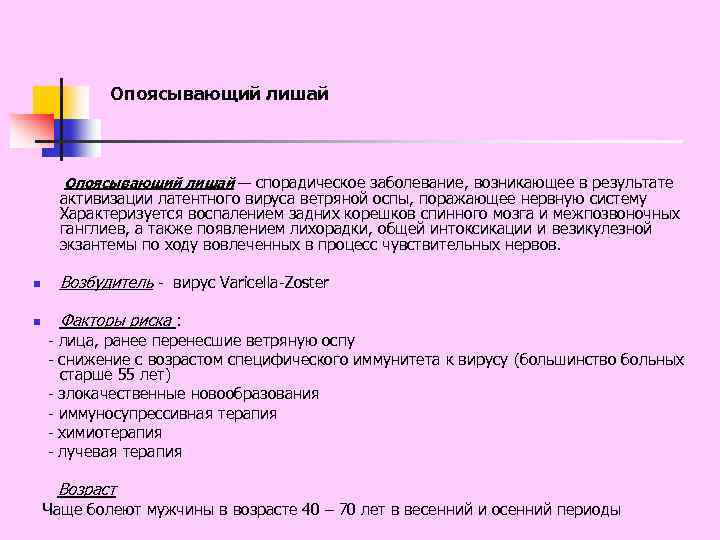

Опоясывающий лишай — спорадическое заболевание, возникающее в результате активизации латентного вируса ветряной оспы, поражающее нервную систему Характеризуется воспалением задних корешков спинного мозга и межпозвоночных ганглиев, а также появлением лихорадки, общей интоксикации и везикулезной экзантемы по ходу вовлеченных в процесс чувствительных нервов. n Возбудитель - вирус Varicella-Zoster n Факторы риска : - лица, ранее перенесшие ветряную оспу - снижение с возрастом специфического иммунитета к вирусу (большинство больных старше 55 лет) - злокачественные новообразования - иммуносупрессивная терапия - химиотерапия - лучевая терапия Возраст Чаще болеют мужчины в возрасте 40 – 70 лет в весенний и осенний периоды

Опоясывающий лишай — спорадическое заболевание, возникающее в результате активизации латентного вируса ветряной оспы, поражающее нервную систему Характеризуется воспалением задних корешков спинного мозга и межпозвоночных ганглиев, а также появлением лихорадки, общей интоксикации и везикулезной экзантемы по ходу вовлеченных в процесс чувствительных нервов. n Возбудитель - вирус Varicella-Zoster n Факторы риска : - лица, ранее перенесшие ветряную оспу - снижение с возрастом специфического иммунитета к вирусу (большинство больных старше 55 лет) - злокачественные новообразования - иммуносупрессивная терапия - химиотерапия - лучевая терапия Возраст Чаще болеют мужчины в возрасте 40 – 70 лет в весенний и осенний периоды